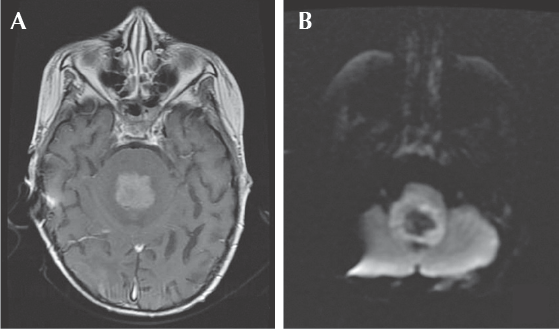

La evolución clínica durante el tratamiento fue tórpida, presentando datos clínicos y radiográficos de disfunción del sistema de derivación ventriculoperitoneal y progresión tumoral (Figura 5), por lo que fueron necesarias distintas intervenciones como el recambio del sistema de derivación e incluso se decidió iniciar radioterapia craneoespinal (25 Gy/15 Gy). A pesar de estas intervenciones continuó con datos de progresión tumoral que requirieron cambiar a un esquema de quimioterapia teóricamente con mayor penetración al sistema nervioso central (similar al FAB/LMB-96)20 agregando una nueva fase de intensificación basada en dosis altas de metotrexato y citarabina.

Figura 5 Progresión de la enfermedad. A) Resonancia magnética contrastada en fase T1, corte axial: lesión con realce heterogéneo posterior a la administración del medio de contraste, condiciona obliteración total de la luz del cuarto ventrículo, así como compresión de puente y bulbo raquídeo. B) Resonancia magnética: realce heterogéneo periférico en el patrón de restricción de la difusión.